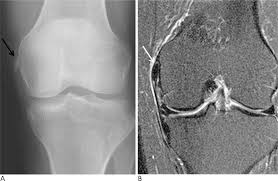

Pellegrini stieda syndrome is a medical problem which is characterized by pain, swelling and inflammation in the knee. It is a common incidental finding on knee radiographs. Pain and restriction of movements. The cause of the knee effusion is unknown. There is a moderately large knee effusion. The diagnosis pellegrini stieda disease was made. Is the presence of a radiological finding of calcification on the medial side of the knee as a consequence. It is likely that this patient has been an active sportsman in the past.

Pain and restriction of movements. The cause of the knee effusion is unknown. It is likely that this patient has been an active sportsman in the past. #foamed #foamrad #radiology #rad #elearnrad #voxelz #varunbabu #drbabu. Pellegrini stieda syndrome is a medical problem which is characterized by pain, swelling and inflammation in the knee. Most of the cases of pellegrini stieda lesions are not symptomatic, and pellegrini stieda syndrome is said to exist when the lesion becomes symptomatic i.e. Ayurvedic treatment is the natural way to treat pellegrini stieda syndrome. Is the presence of a radiological finding of calcification on the medial side of the knee as a consequence. The diagnosis pellegrini stieda disease was made. It is a common incidental finding on knee radiographs. With the ayurvedic treatment, it is possible to avoid surgery. This occurs due to the deposition of calcium on the inner side of the knee. Learn about this soft tissue calcification around the knee joint.

Pellegrini stieda syndrome is a medical problem which is characterized by pain, swelling and inflammation in the knee. The diagnosis pellegrini stieda disease was made. Learn about this soft tissue calcification around the knee joint. The cause of the knee effusion is unknown. There is a moderately large knee effusion. Pain and restriction of movements. Is the presence of a radiological finding of calcification on the medial side of the knee as a consequence. It is a common incidental finding on knee radiographs. Most of the cases of pellegrini stieda lesions are not symptomatic, and pellegrini stieda syndrome is said to exist when the lesion becomes symptomatic i.e. #foamed #foamrad #radiology #rad #elearnrad #voxelz #varunbabu #drbabu. It is likely that this patient has been an active sportsman in the past. There is evidence of osteoarthritis. This occurs due to the deposition of calcium on the inner side of the knee.